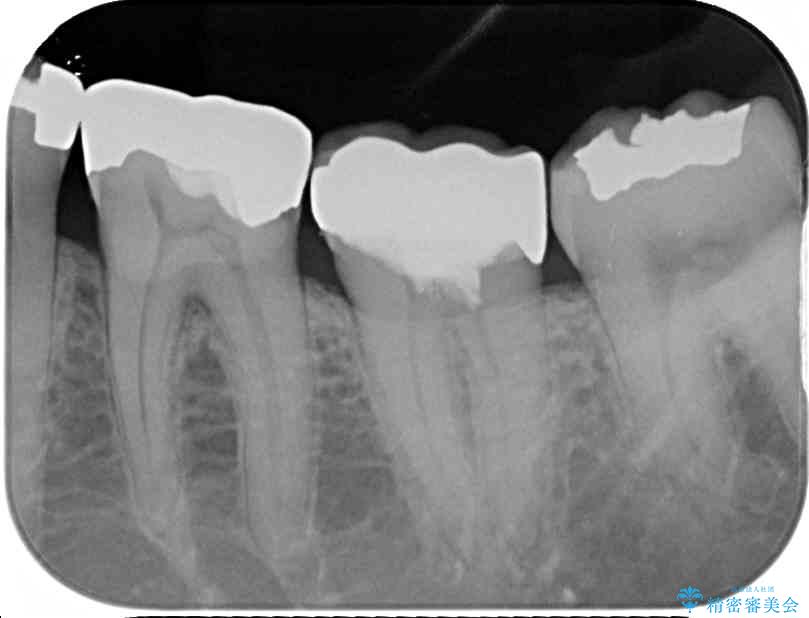

診査をしたところ、神経組織に影響を及ぼすような大きな虫歯があることが分かりました。

虫歯が歯髄腔(神経の部屋)に達している可能性が非常に高かったため、炎症を起こしている神経組織を部分的に切除し、歯根部分の神経組織を保存する治療法が望ましいと考えられました。

• 治療をしても違和感の続く奥歯 神経を極力残した虫歯治療 治療前画像